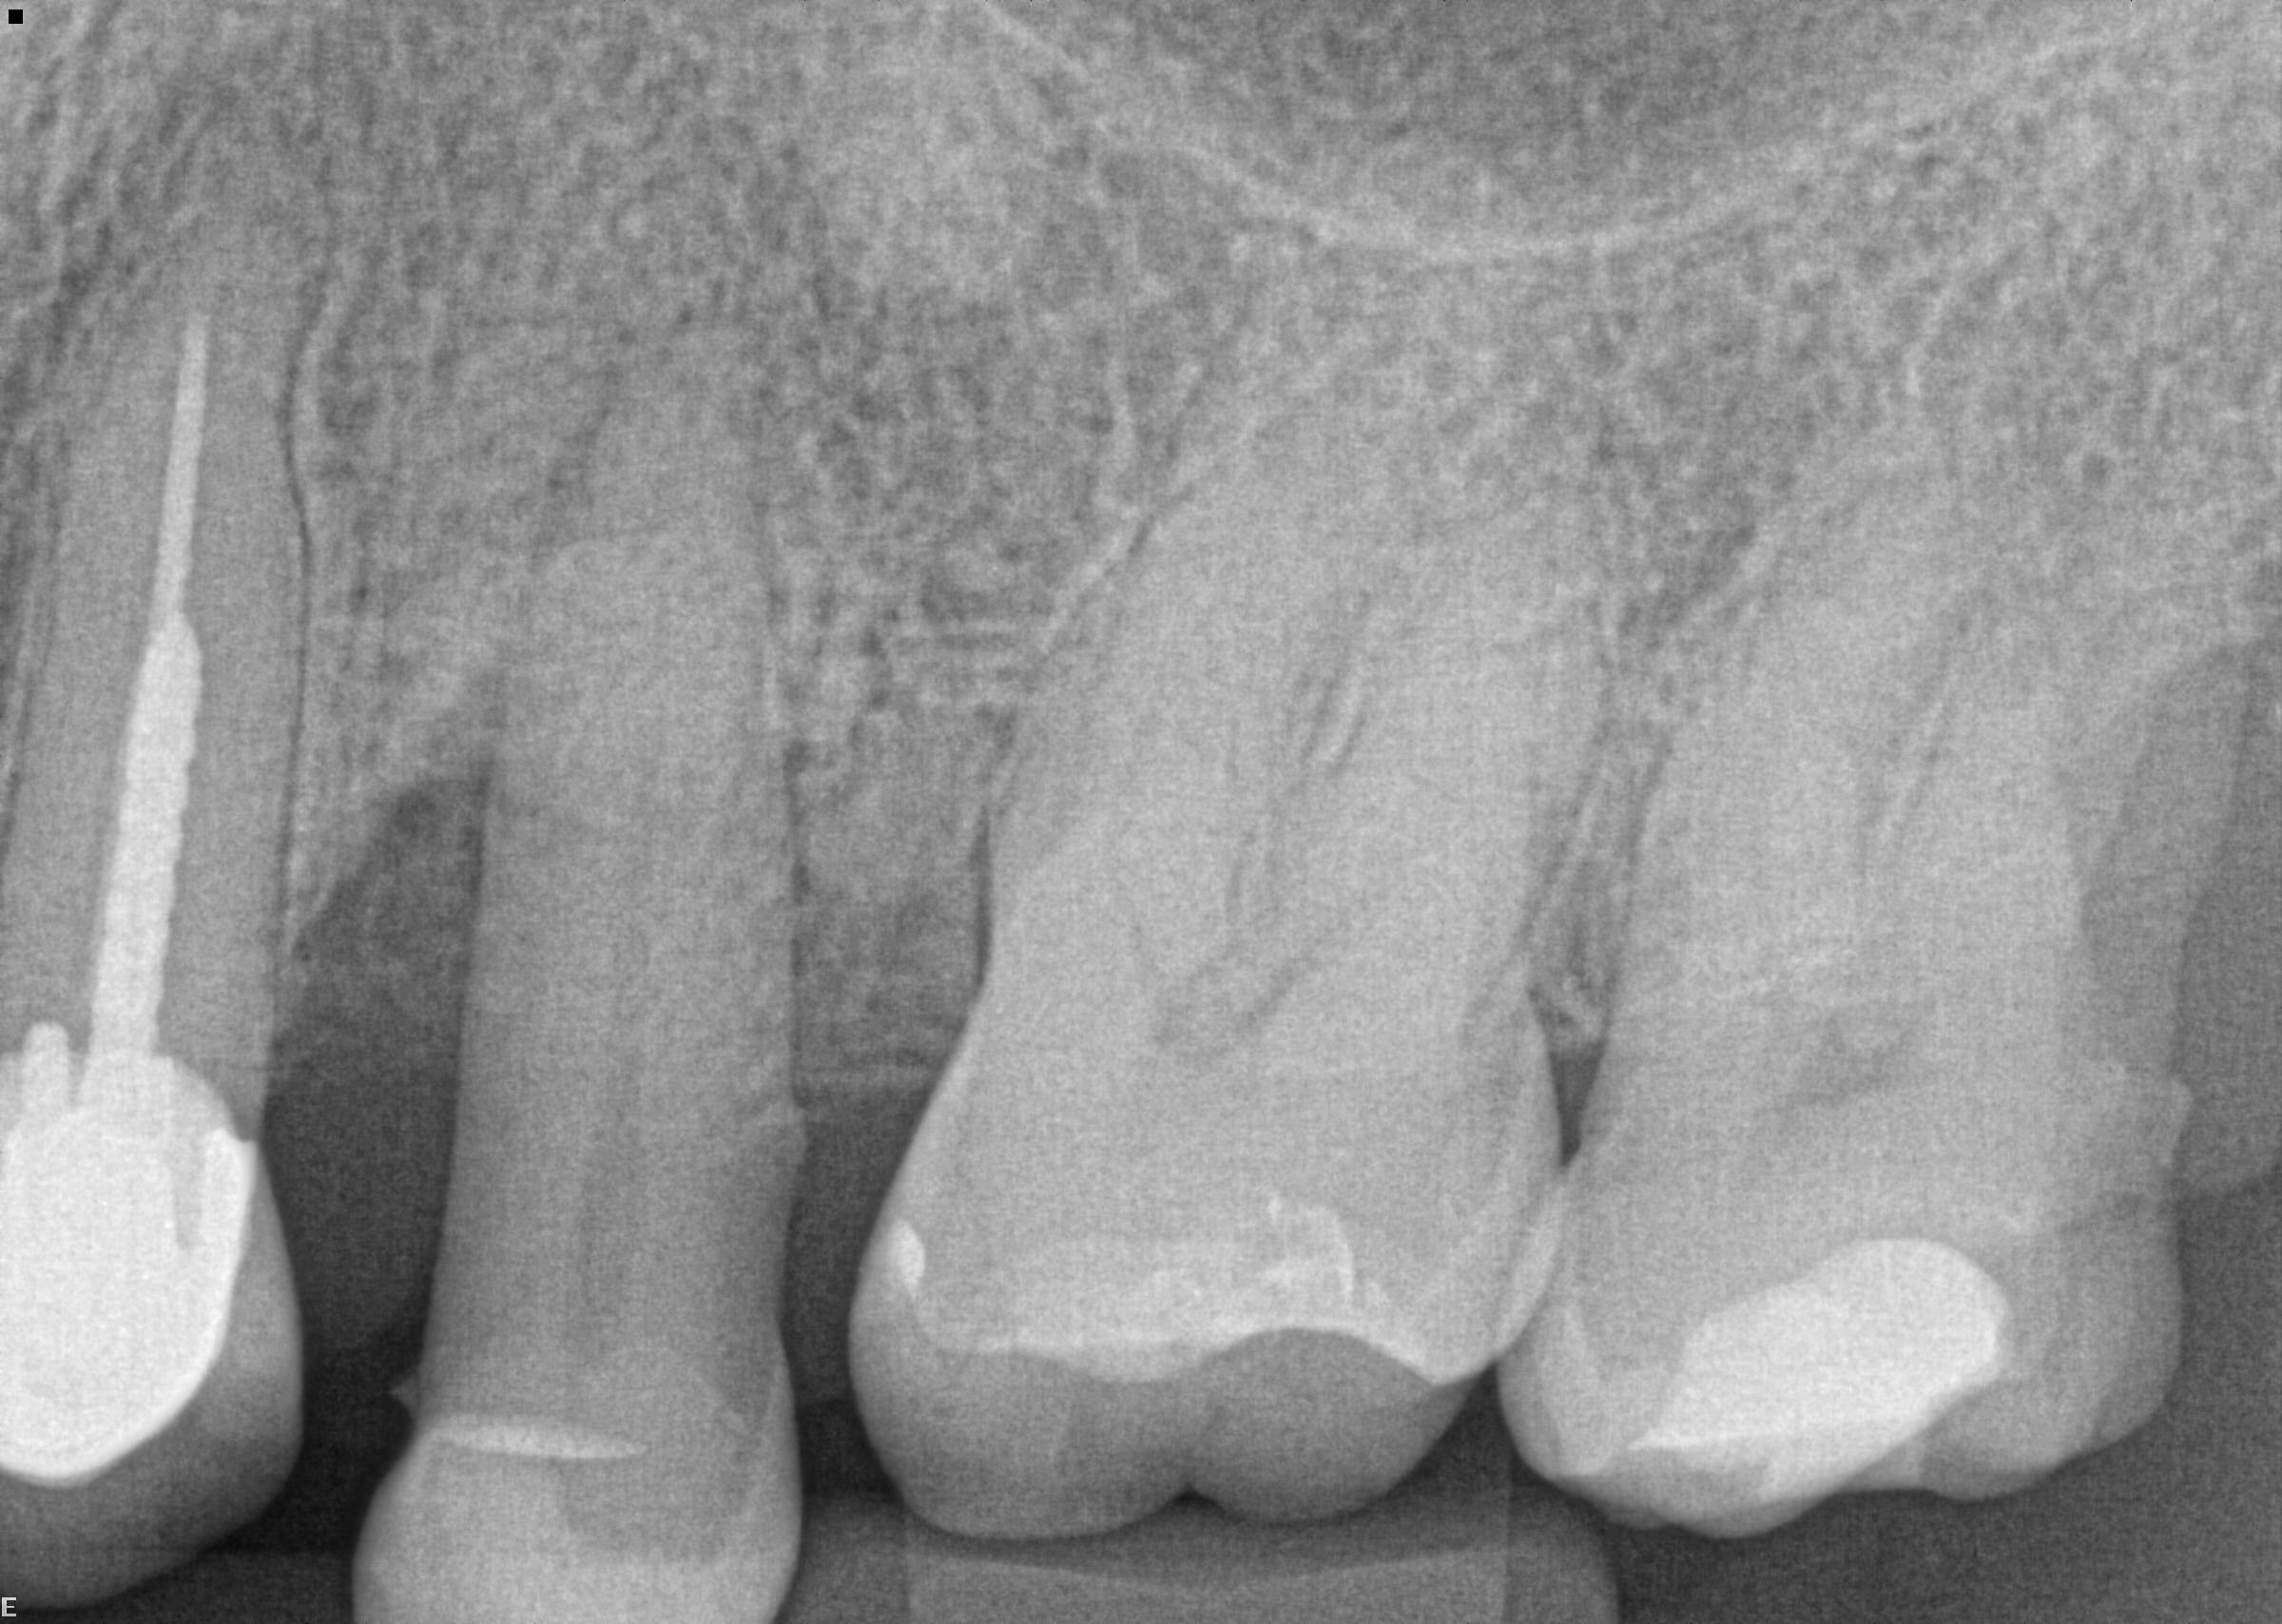

14 / 50

14. (Select ONE OR MORE correct answer)

Which of the following is true regarding dental implant at site 3.6?